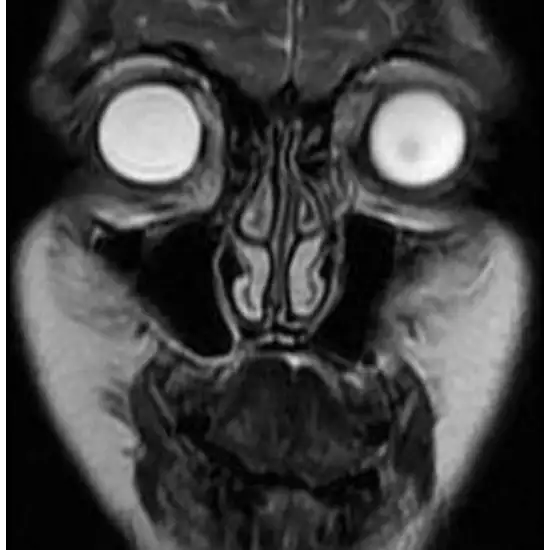

mri screening of face

The MRI Face scan obtains images of the human body's internal structures and organs.

An MRI scan of the face is an imaging technique used to aid in the identification of numerous diseases and ailments affecting the bones, joints, and soft tissues of the face. A face MRI may also be conducted as a pre-operative and post-operative treatment to assess surgical outcomes and healing processes.